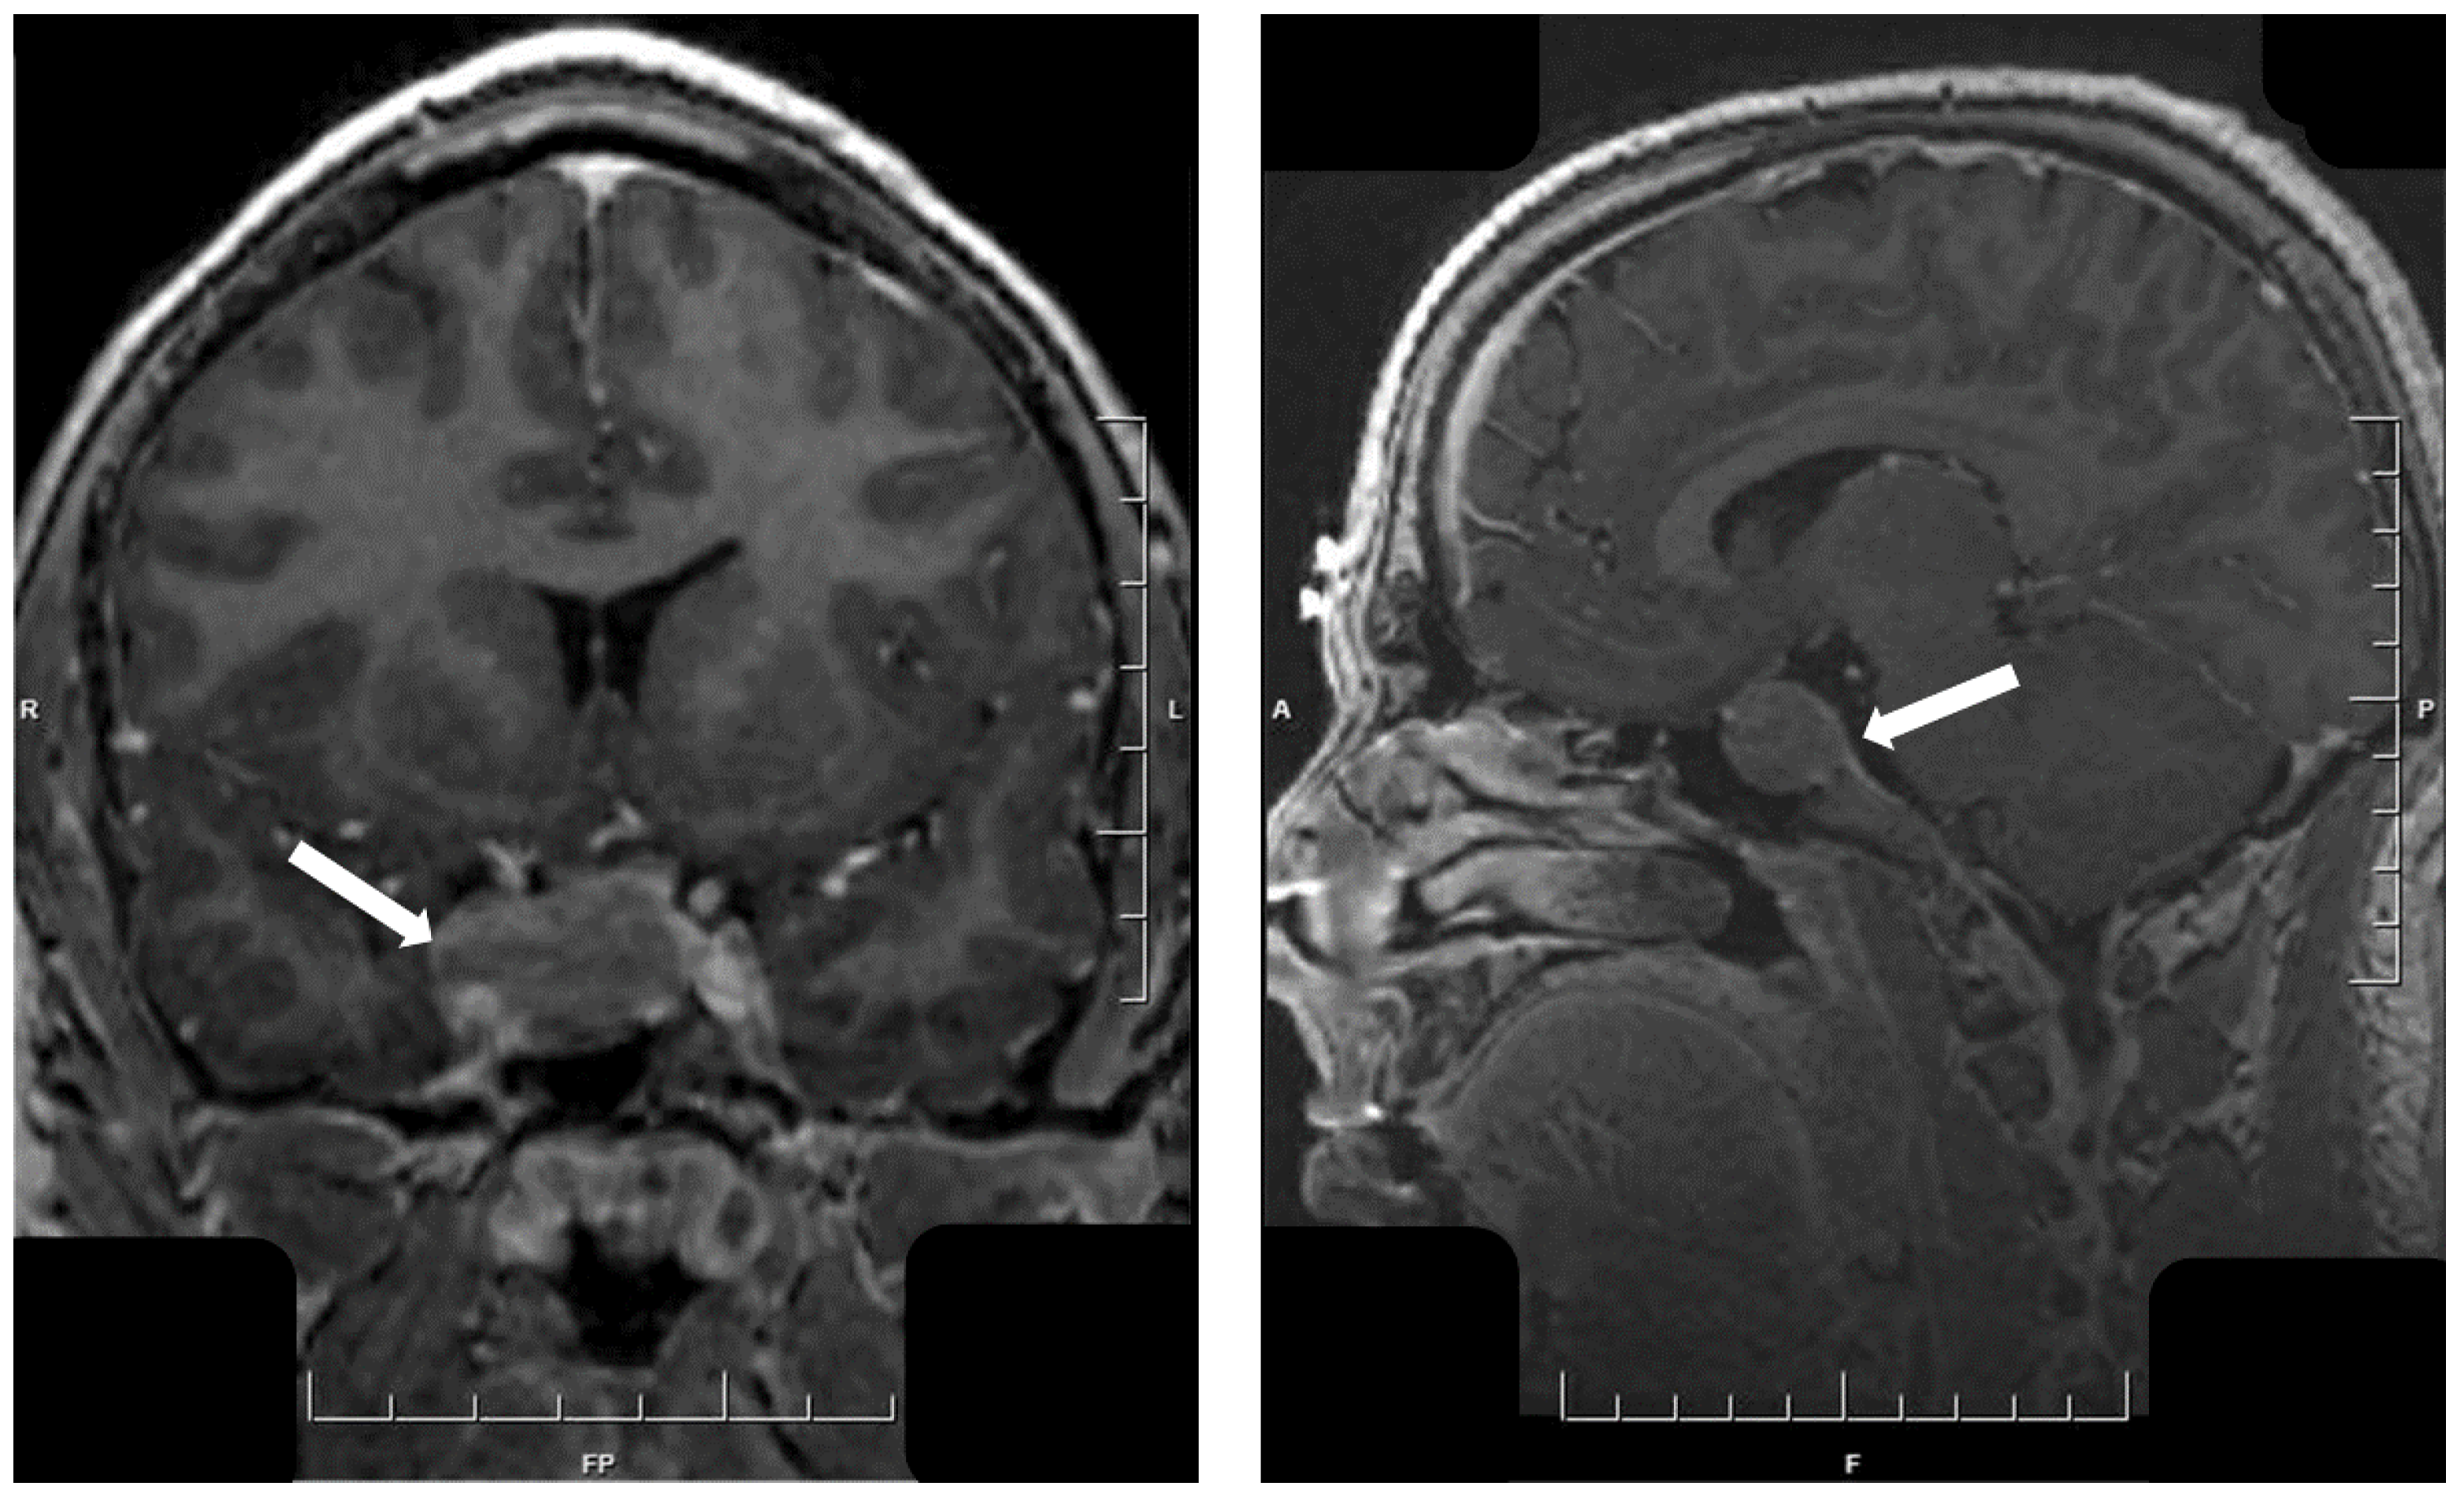

- Asa, S.L.; Mete, O. Hypothalamic Endocrine Tumors: An Update. J. Clin. Med. 2019, 8, 1741. [Google Scholar] [CrossRef]

- Asa, S.L.; Scheithauer, B.W.; Bilbao, J.M.; Horvath, E.; Ryan, N.; Kovacs, K.; Randall, R.V.; Laws, E.R.; Singer, W., Jr.; Linfoot, J.A.; et al. A case for hypothalamic acromegaly: A clinicopathological study of six patients with hypothalamic gangliocytomas producing growth hormone-releasing factor. J. Clin. Endocrinol. Metab. 1984, 58, 796–803. [Google Scholar] [CrossRef]

- Puchner, M.J.A.; Lüdecke, D.K.; Saeger, W.; Riedel, M.; Asa, S.L. Gangliocytomas of the sellar region—a review. Exper. Clin. Endocrinol. 1995, 103, 129–149. [Google Scholar] [CrossRef] [PubMed]

- Cossu, G.; Daniel, R.T.; Messerer, M. Gangliocytomas of the sellar region: A challenging diagnosis. Clin. Neurol. Neurosurg. 2016, 149, 122–135. [Google Scholar] [CrossRef] [PubMed]